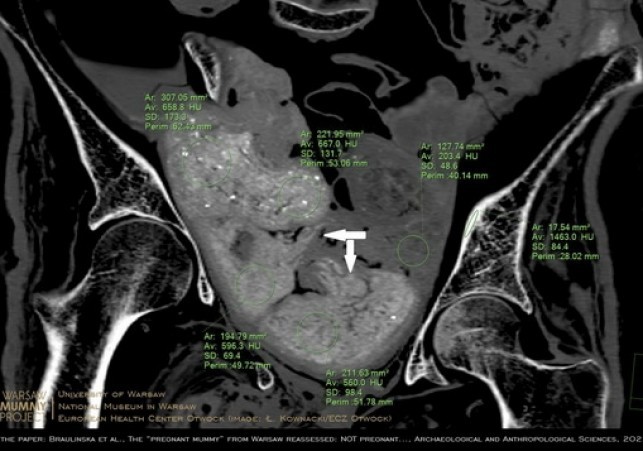

W lipcu 2022 ukazała się bogato ilustrowana publikacja w "Archeological and Anthropological Sciences" (DOI: 10.1007/s12520-022-01598-z), w której inny zespół badaczy z WMP dowodzi, że zmumifikowana kobieta z pewnością nie zawiera w sobie płodu. Świadczą o tym przede wszystkim obrazy precyzyjnie zrekonstruowanej zawartości miednicy oraz wyniki badań porównawczych starożytnych płodów egipskich.

Naukowcy ustalili, że w miednicy wcale nie ma płodu - jak sugerowali autorzy doniesienia z 2021 r. - ale cztery pakunki.

"Umieścili je tam starożytni balsamiści. W zawiniątkach znajduje się najprawdopodobniej co najmniej jeden zmumifikowany organ zmarłej. To znana praktyka w starożytnym Egipcie" - podkreśliła Braulińska. W pozostałych być może są fragmenty ciała lub inne pozostałości po procesie mumifikacji. Jest też inna opcja - balsamiści umieszczali w mumiach zawiniątka po to, aby utrzymać kształt ciała po procesie mumifikacji.

To właśnie trzy z czterech pakunków w miednicy poprzedni zespół zinterpretował jako płód. O tym, że kobieta nie była w ciąży, świadczą też ilościowe pomiary gęstości radiologicznych, a także wzajemne relacje geometryczne pakunków oraz porównawcza charakterystyka materiałów znajdujących się wewnątrz mumii - argumentują badacze w nowo opublikowanym artykule.